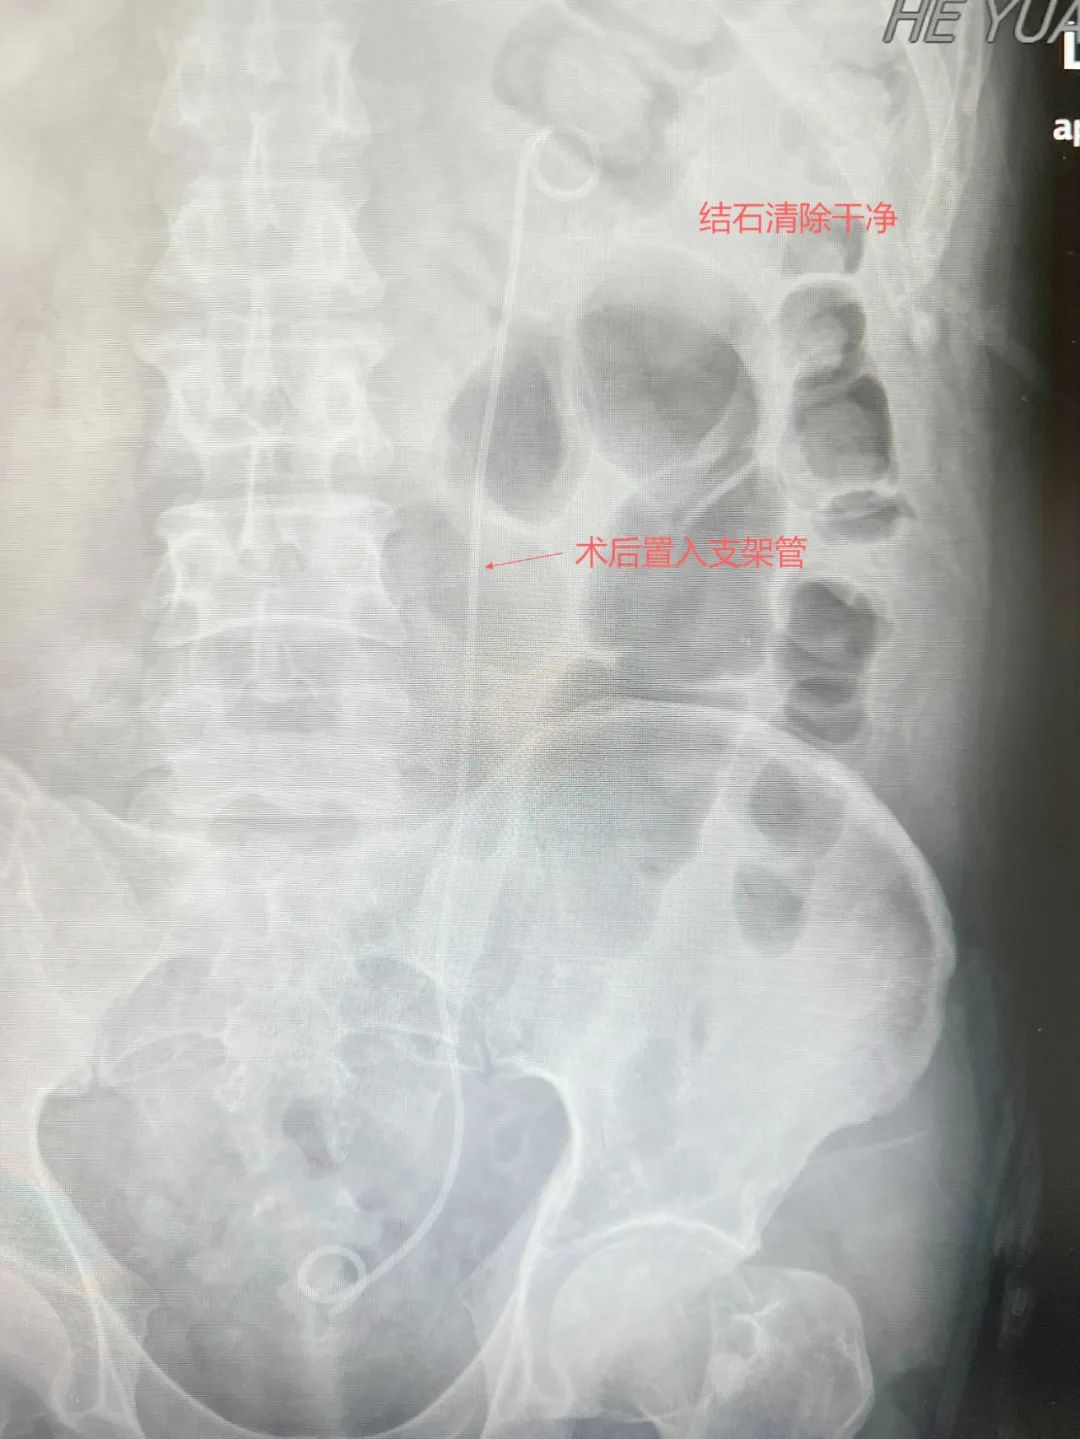

▲术后复查腹平片

面对这一复杂病例,毕学成主任带领泌尿外科团队迅速制定治疗方案。经详细检查发现,患者左肾结石不仅体积大、数量多,由于经历多次手术,结石与肾实质形成“钢筋混凝土”式粘连,传统术式极易引发大出血。毕学成主任带领多学科团队采用“经皮肾镜+输尿管软镜双镜联合术式”:先在超声引导下建立0.6厘米微创通道粉碎主体结石,再通过自然腔道置入输尿管软镜清除死角残石。两台高精设备“天地配合”,仅历时2小时将结石彻底“剿灭”,术中出血仅50毫升。术后复查显示患者左肾结石100%清除,困扰多年的腰痛、感染症状彻底消失。术后次日,向先生就可以下床活动,向先生激动表示:“跑了那么多医院,只有这里给了我重生的希望!感谢毕主任和团队的高超技术!”